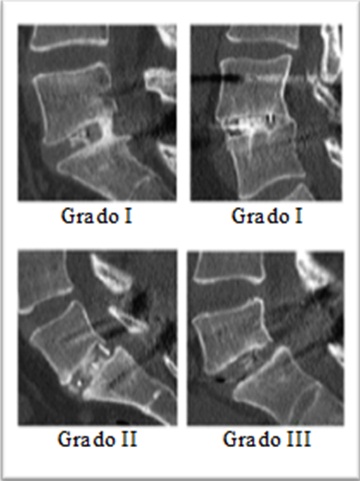

IntroducciónLa fusión quirúrgica de la columna lumbar es un método muy utilizado para el tratamiento de la inestabilidad segmentaria lumbar dolorosa. En la actualidad, las dos técnicas de fusión instrumentada más utilizadas son la fusión posterolateral con tornillos pediculares y la fusión circunferencial mediante asociación de caja intersomática. Si bien hay evidencia de que la asociación de dispositivos intersomáticos aumenta la tasa de fusión, la mayoría de los estudios no discriminan si esta se produce solo de forma posterolateral o si se asocia una fusión anterior. El objetivo de este trabajo es determinar si existe fusión ósea real a nivel de las cajas intersomáticas o si estas actúan solo como espaciadores.Material y métodosSe analizaron 28 pacientes con patología de la columna lumbar sometidos a artrodesis lumbar circunferencial en un solo nivel entre mayo de 2007 y enero de 2012, mediante tomografía computarizada posquirúrgica para valorar la presencia o no de artrodesis anterior. Se efectuó un estudio de valor terapéutico, descriptivo, de observación (nivel de evidencia IV); mediante evaluación estadística se realizó un análisis de frecuencias para describir la proporción de casos con fusión anterior.ResultadosSe detectó una tasa de fusión del 92,86% y falta de fusión radiológica anterior en el 7,14% de los pacientes.ConclusionesHay una alta tasa de fusión anterior a nivel de las cajas intersomáticas; de este modo, se demuestra que dichos dispositivos actúan como medios de fusión y no solo como espaciadores.